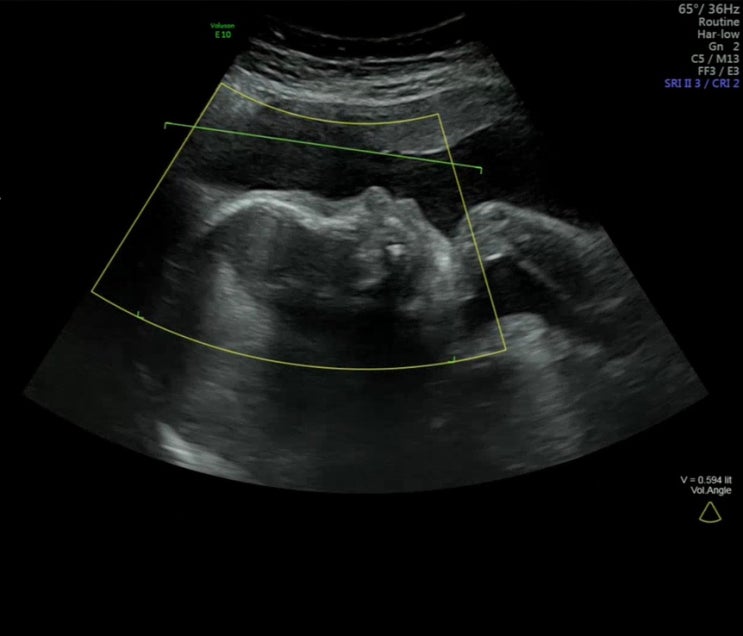

임신 24주~27주차 기록_임당검사, 입체초음파

임신 24주~27주차 기록 애기가 근육이 많이 붙었는지 태동이 점점 잘 느껴져 신기하고 재밌는 임신 중기 끝...